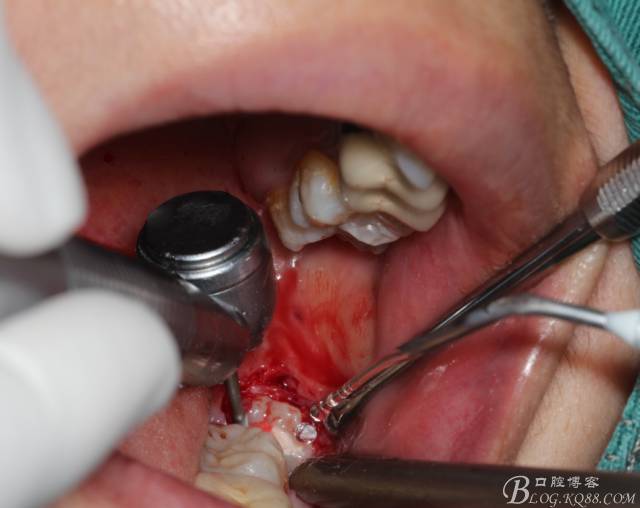

角度鍋輪機結(jié)合冷鹽水冷卻分冠

640 (11).jpg

分冠完成

640 (12).jpg

取出阻力部分冠

在取出阻力冠后,嘗試性看能取出全部的牙體不,就是取不出也能整體撬動牙根。

計劃總趕不上變化,何況是充滿變異的智齒。由于可操作空間較小,原來計劃橫向分根改成矢狀分根。